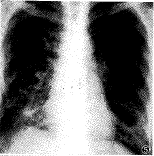

囊状PAVMs通常具有典型X线平片征象,表现为孤立或多发的类圆形阴影,阴影直径大小不等 ,密度均匀,边缘清晰,或有浅分叶;扩张增粗的供血动脉及引流静脉连于阴影,供血动脉 与肺门相连;该阴影一般不增大或仅缓慢增大。根据上述特点,结合临床资料多数囊状PAVM s可作出明确诊断(图1)。不典型者平片诊断有一定困难,例如本组2例复杂型多支供血囊状肺动静脉瘘,平片表现为大片致密影,很难根据X线平片作出正确诊断(图3)。弥漫型肺小动静脉瘘,多缺乏典型X线平片 征象,可表现为肺叶或肺段分布斑点状阴影(图5),也可表现为肺纹理增强、扭曲(图8),有 的病例平片无阳性所见。因此,弥漫型肺小动静脉瘘,X线平片诊断困难。

图5~7 X线平片示两下肺斑点状阴影,选择性左下肺动脉及右下肺动 脉造影,示两下肺弥漫型肺小动静脉瘘